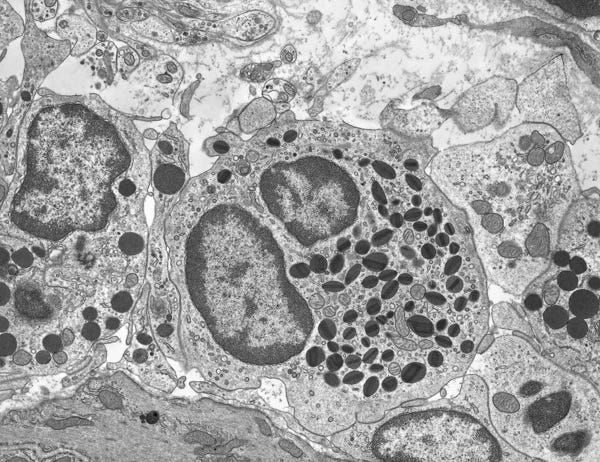

Graves’ disease is the immunological production of a thyrotropin receptor antibody, leading to too much thyroid hormone heightening the metabolism unsustainably, thinning the bones, bulging the eyes, and skipping heartbeats. Rheumatoid arthritis begins with inflammation of the synovial tissues, the delicate connective tissue lining, normally a microscopic 2-3 cells thick. Sjögren disease starts with white blood cells breaching and damaging the salivary and tear glands, drying every damp orifice. In Lupus, T and B cells become overactive, producing autoantibodies the nucleic material of the cells and the proteins of cellular membranes.

In most chronic illness, the medical model blames the patient for not fighting harder or complying with protocols. In autoimmune disease, blame is already etched into DNA, a birth-curse awakened through environmental triggers. Autoimmune disease begets further autoimmune disease, because a revved engine does not only power one part of the car, and the patient becomes an unsolvable problem that does not fit neatly into any one medical specialty. It can manifest in every bodily system, from the gastrointestinal (e.g., Crohn’s) to the brain (e.g., Autoimmune encephalitis, Multiple Sclerosis).

But most autoimmune disease mechanisms of action are side effects, not direct immunological intent, and medical metaphors fail to capture the complex series of dominoes at play. The immune system isn’t an angry beast biting it’s own fingers to spite it’s hands or a scared inner child. It cannot be calmed by meditation, somatic therapy, or (as a specialist once suggested to me) watching soothing TV reruns. It is more like a mechanical component in a complex machine allowed to run too hot and inefficient until a vital series of things break.